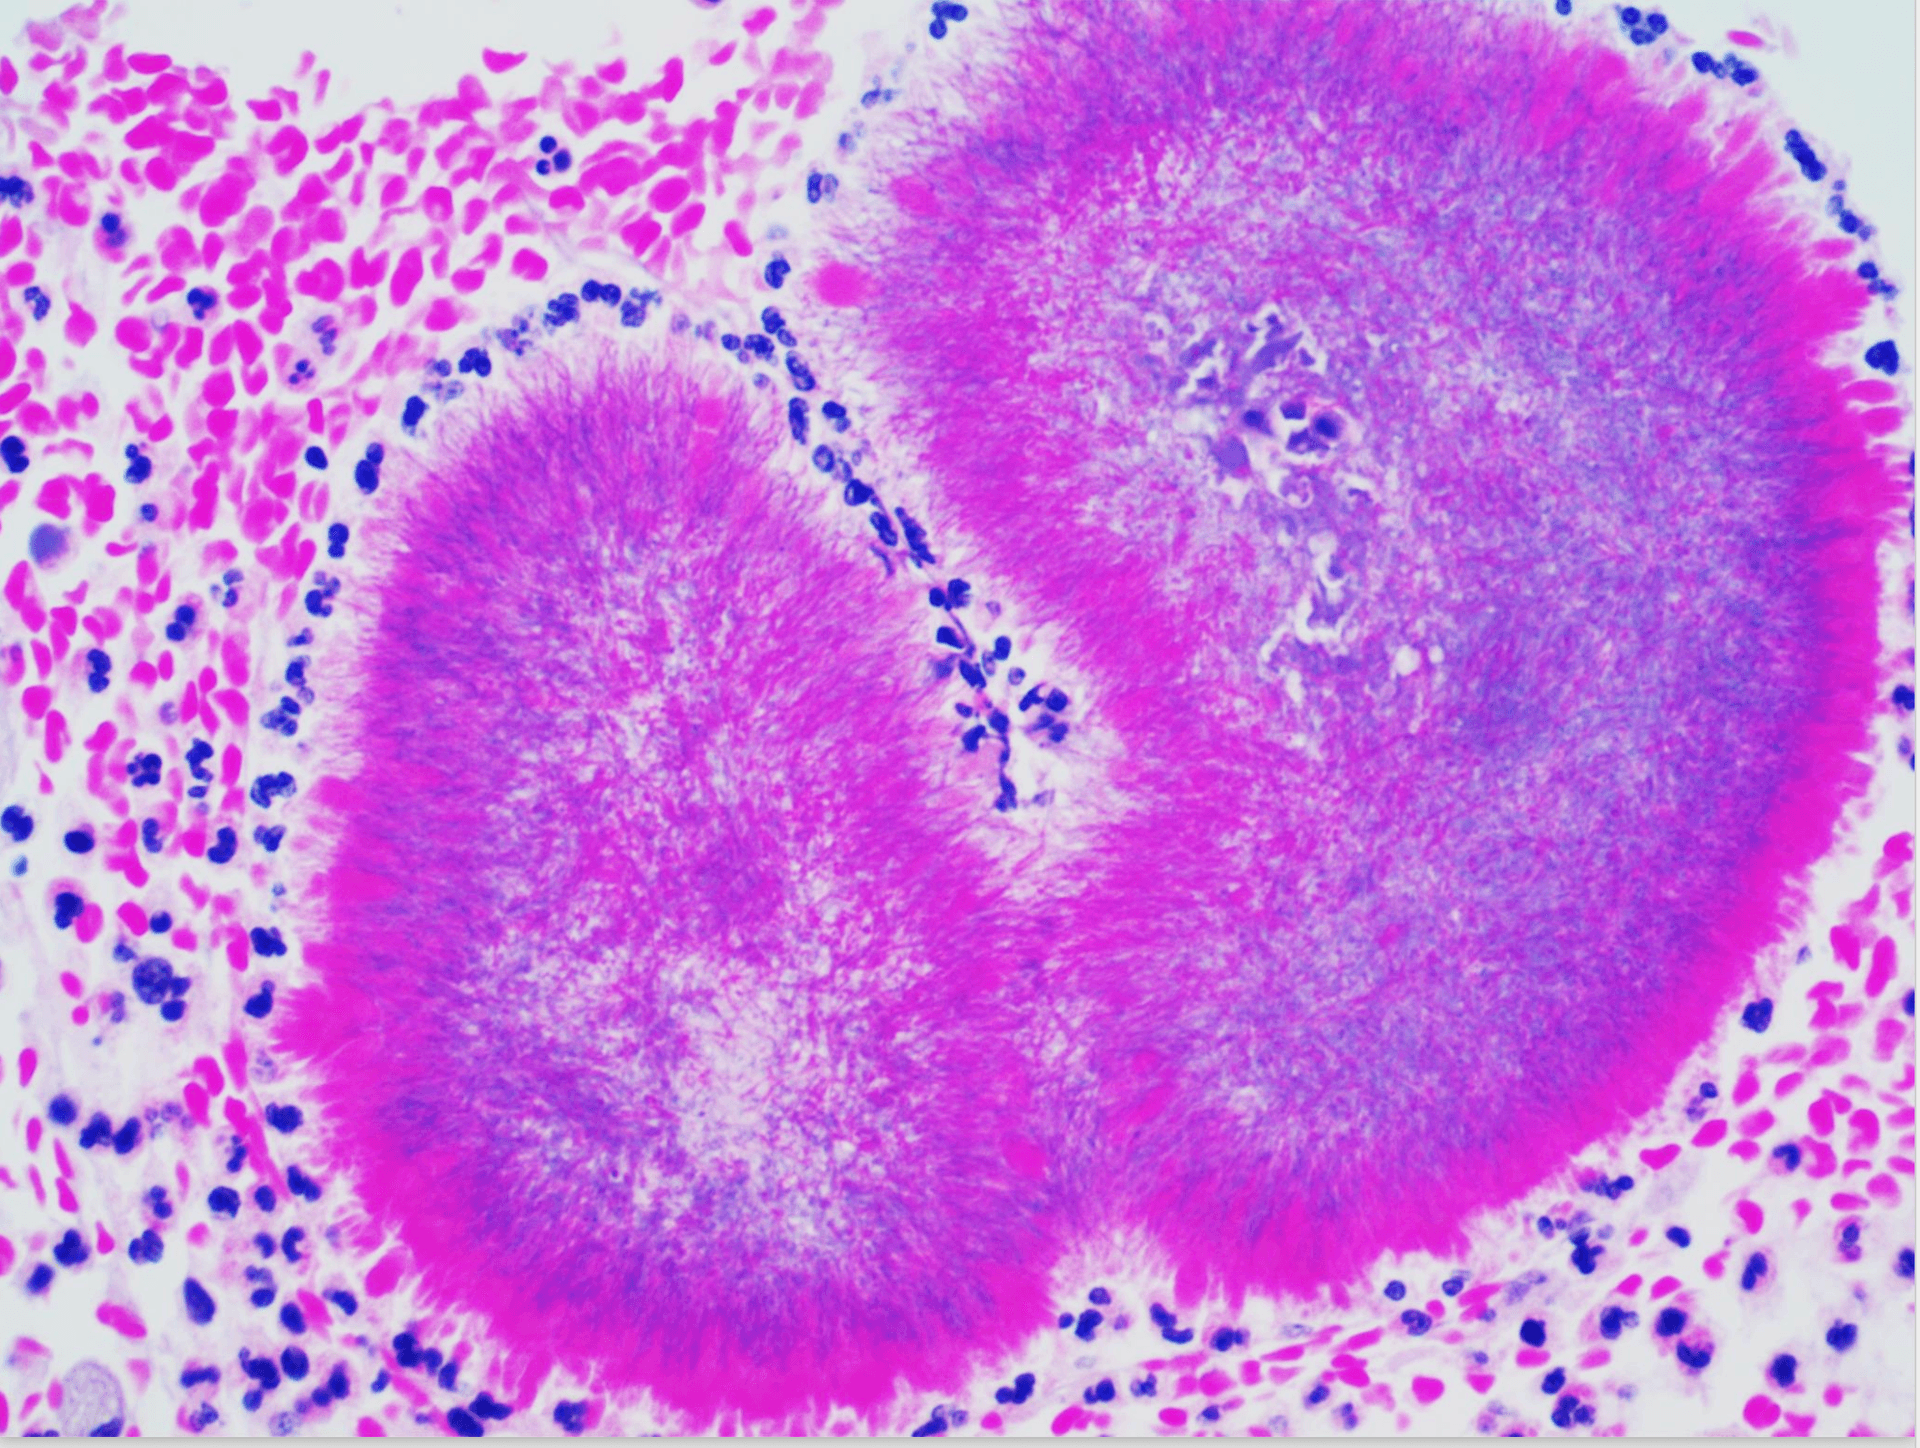

CT and tissue pathology were obtained because malignancy was initially suspected. Imaging showed an infiltrative soft-tissue process with mass-like appearance. Histopathology demonstrated sulfur granules with branching filamentous gram-positive organisms, consistent with actinomycotic infection.